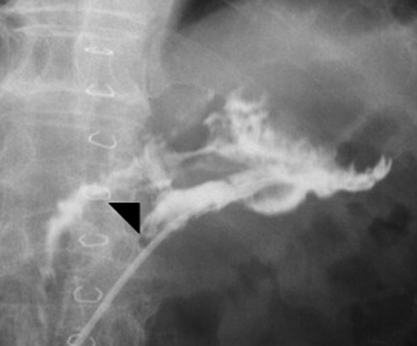

現病歴①:2016年10月,腹痛・下痢精査の下部消化管内視鏡検査(以下,CFSと略記)で全周性の横行結腸癌と診断され自己拡張型金属ステントを留置,上部消化管内視鏡では胃角後壁にIIa+IIc病変を認め胃癌と診断された.2017年1月に手術目的に入院,第4病日に横行結腸切除+幽門側胃切除術を施行した.病理組織所見は大腸癌(T,circ,type 5,40×35 mm,tub2,pT4a,int,INFb,ly0,v2,PN1a,pN0,pPM0(75 mm),pDM0(80 mm),pT4aN0M0,pStage II)および胃癌(M,Post,Type 0-IIc,17×9 mm,tub1,pT1a,ly0,v0,pN0,pPM0(27 mm),pDM0(65 mm),pT1aN0M0,pStage IA)であった.第17病日にドレーン造影で残胃十二指腸吻合の縫合不全を認め(Fig. 1),ドレーン排液の培養よりSerratia marcescensを検出した.第27病日に38.0°Cの発熱を認め,Serratia感染と中心静脈カテーテル感染を念頭にceftriaxone(以下,CTRXと略記)およびVCM点滴を開始した.第36病日に38.2°Cの発熱に加えて腹部膨満,右季肋部痛が出現した.第39病日の血液検査ではWBC 49,620/μl,CRP 19.9 mg/dlの高度炎症反応亢進とBUN 23.6 mg/dl,Cre 1.01 mg/dlの軽度腎機能障害を認め(Table 1),腹部単純レントゲンでは右側結腸の拡張と回腸の一部にもガス貯留を認めた(Fig. 2).腹部超音波検査では胆囊腫大や壁肥厚を認めず,胆囊炎は否定的であった.縫合不全からの敗血症と診断し,CTRXを増量した.炎症反応の改善を認めたためCTRXが有効と判断し,第42病日にVCMを中止したが,第43病日にAST 690 U/l,ALT 471 U/lの肝機能障害が出現した.CTRXによる肝障害を疑い,抗生剤をcefozopranに変更した.その後肝機能障害は徐々に改善し排便は認められたが,37°C台の稽留熱と軽度の腹部膨満は継続した.下痢は認めなかった.第46病日に38~39°Cの弛張熱を認め,腹部骨盤造影CTで全結腸および直腸の壁肥厚像を認め(Fig. 3a~f)腸炎と診断した.第47病日のCFSで直腸からS状結腸にかけてびまん性に偽膜の付着を認め偽膜性腸炎と診断し(Fig. 4),同日の血液検査でAlb 2.1 g/dl,WBC 13,750/μl,臍部に圧痛を認めたが腹膜刺激症状は認めないため,American College of Gastroenterology(以下,ACGと略記)ガイドラインの重症(severe disease)と診断し,VCM 125 mg×4回/日を開始した.

Fistelography demonstrates the leakage from gastroduodenal anastomosis (arrowhead).